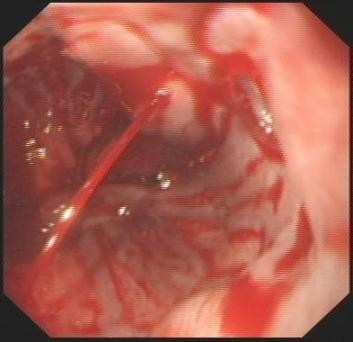

⑤ESD

随着内镜微创技术的发展,越来越多的早期消化道癌、癌前病变及胃肠黏膜下疾病可完全在内镜下予以切除,免除了更大的手术创伤,这就是内镜黏膜下剥离术ESD(endoscopic submucosal dissecfion)

该治疗具有不改变消化道解剖结构、不开刀、体表无创口、创伤、出血少、恢复快等优势,是近年来国际、国内最新兴起的内窥镜下微创治疗手段之一,适用于食管、胃、十二指肠等上消化道及结、直肠的黏膜下良性肿瘤、黏膜的早期癌变以及具有癌变倾向病变的切除治疗。因其特殊的微创优势,得到广大医生及患者的推崇,是消化道黏膜及黏膜下病变治疗的新兴发展趋势。我中心已经开展该项技术,技术成熟,并还开展了经口内镜下肌切开术POEM、内镜经粘膜下隧道肿瘤切除术STER、粘膜下隧道内镜剥离术ESTD,术后病人随访,恢复良好。

Ⅰ、ESD的治疗效果如何?

ESD治疗胃早癌可实现较高的整块切除率(92%~97%)和完整切除率(73.6%~94.7%),5年总生存率和5年疾病生存率分别为96.2%~97.1%和100%。

Ⅲ、POEM治疗贲门失弛缓症

Ⅳ、ESTD治疗多灶性复发型食管早癌

Ⅴ、ESTD治疗超低位大面积直肠早癌

Ⅵ、STER治疗食管固有肌层肿瘤